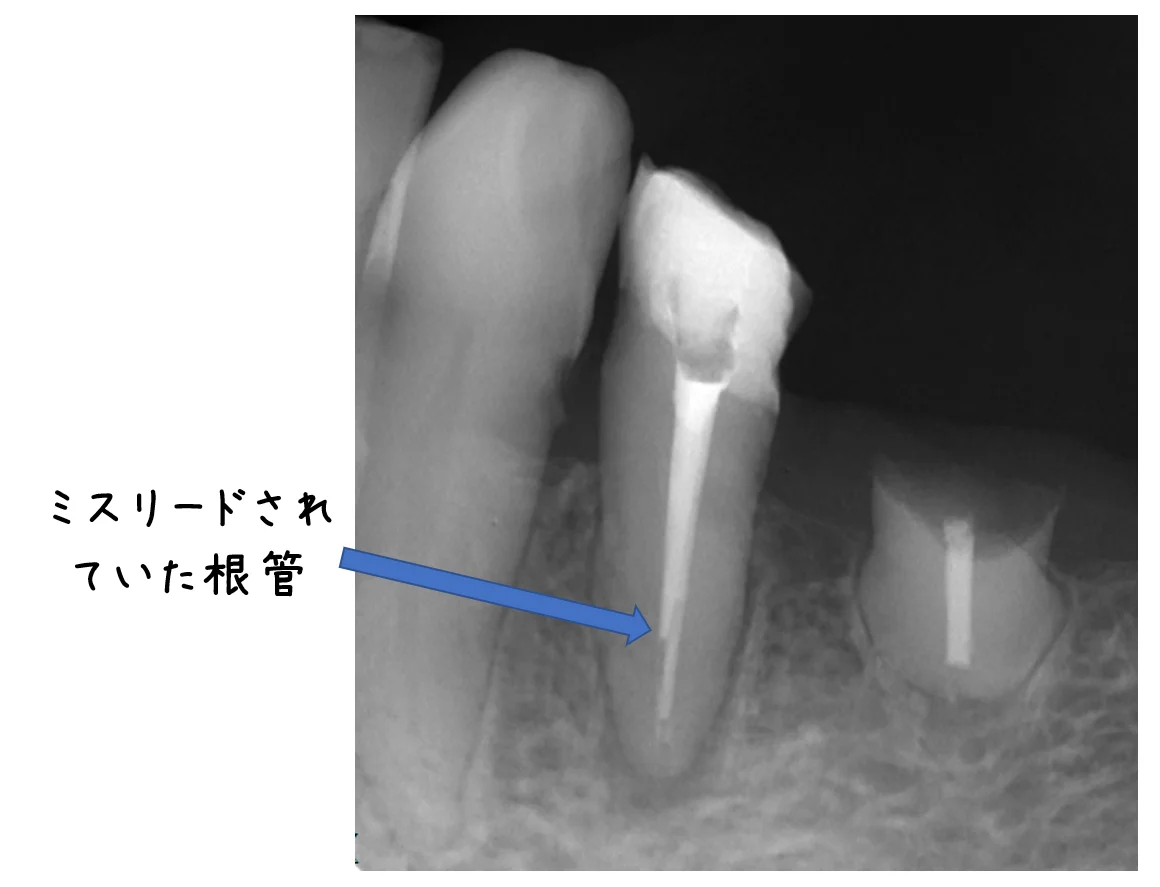

術後のレントゲンがこちらです。

お薬が2本見えていますが、そのうち短い方が明後日な方向にミスリードされていた根管です。